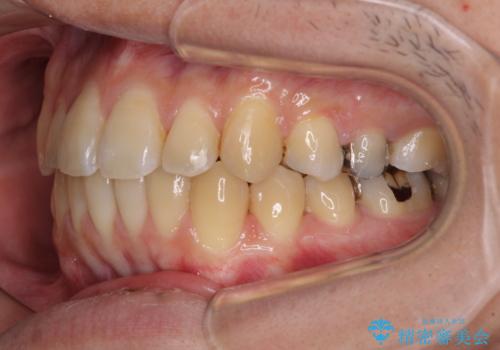

前歯のクロスバイトをインビザラインで矯正治療

- 前歯のデコボコとクロスバイトを気にして来院された患者様です。

前歯を早く整えたいとの希望があったので、ワイヤー矯正にて短期間でクロスバイトを解消し、その後インビザラインにて整えることとしました。

インビザラインによる前歯のクロスバイト改善におけるリスクとして、前歯歯髄充血・歯髄壊死が挙げられます。

ワイヤー矯正を併用する目的として、短期間でデコボコやクロスバイトを改善する他に、歯髄充血リスクを低減させるというものがあります。